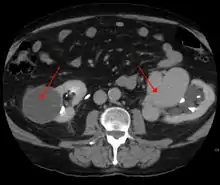

AVMs can occur in various parts of the body:

- brain (cerebral AV malformation)

- spleen[8]

- lung[9][10]

- kidney[11]

- spinal cord[12]

- liver[13]

- intercostal space[14]

- iris[15]

- spermatic cord[16]

- extremities – arm, shoulder, etc.